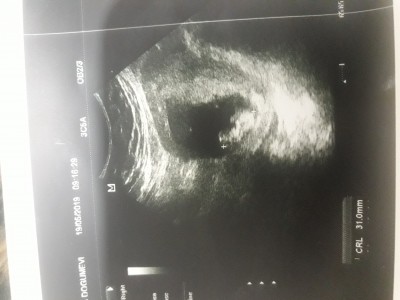

2 oğlum var bu 3. Gebeliğin henüz cinsiyetini öğrenemedim tecrübeli kişilerden tahmin alabilir miyim ?

Gebelik haftası 14

• Kız gbi duruyor:angel:

Anladım bu ultrasonda tam 14 haftalikmi bana çok küçük geldi

Küçük canım 14. Haftaya yeni girdik başka ultrason resmi yoktu elimde 2li testte hiç anlaşılmıyor resim

Haa anladim canım çünkü 14 haftalık gbi durmuyor o yüzden sordum

14 hhaftalik doktorlar bile cok bilmezken kucucuk bebise bakip tahmin yurutmek biraz sacma  cok kucuk daha :)

O kadar çok merak ediyordum ki bende :) çok araştırdım nub teorisi işte hurafeler ikinci gebeliğim benimde  kafa yapısı kese vesayre kız gibi duruyor ama tam bu haftada ultrason foto olsaydı belki daha iyi tahmin edebilirdim sağlıklı olsunlar da rabbim hayırlısıyla kucağımıza almayı nasip etsin erkek kız hayırlısı